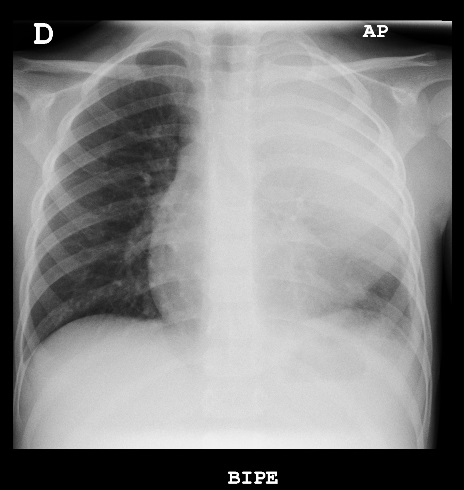

Niño de cuatro años con fiebre de siete días de evolución, diagnosticado de neumonía en el lóbulo superior izquierdo, que ingresa en el hospital con cefotaxima por vía endovenosa; tres días más tarde continua febril y presenta empeoramiento respiratorio con necesidades de oxígeno suplementario. Se realiza una nueva prueba de imagen donde se observa un derrame pleural que ocupa todo el hemitórax izquierdo, alcanzando un espesor máximo de hasta 22 mm (Fig. 1), por lo que se añade clindamicina al tratamiento y se programa drenaje con tubo de tórax. Bioquímica de líquido pleural: parámetros de exudado y antígeno de Streptococcus pneumoniae positivo. Después de diez días recibe el alta a domicilio por su mejoría progresiva, para posterior control en consultas externas.

| Figura 1. Consolidación del lóbulo superior izquierdo acompañado de derrame pleural que ocupa todo el hemitórax ipsilateral |